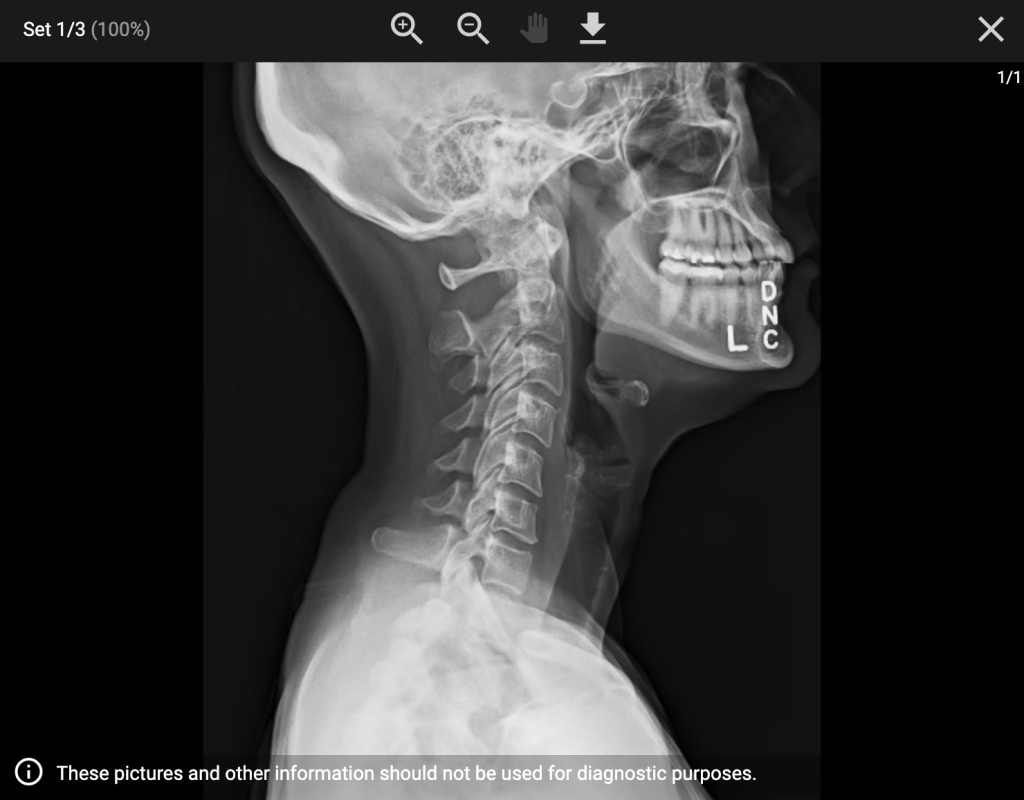

Pain in the Neck – September 6, 2023

Before we left for Utah, I noticed my neck was kinked. I assumed it was just a minor thing that would work itself out, so I ignored it.

But weeks later, it was still there—worse, in fact—and now causing brutal headaches. Normally I avoid chiropractors and myopractors until I absolutely can’t take it anymore... and I was getting close. But then a thought hit me: maybe I should check with my oncologist first—just to be safe.

When I asked him, he said he didn’t want me getting an adjustment without a CT scan first. So I canceled my appointment and got scanned.

Thankfully, nothing concerning showed up.

No FDG avid disease in the neck. (I had asked them to look because of the pain I've been having there.)